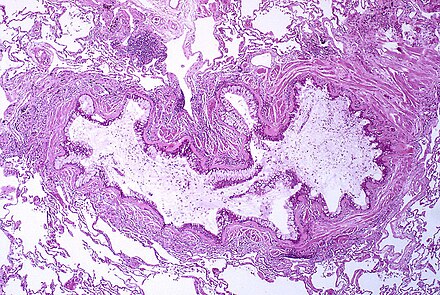

A 59-year-old male patient with a non-small cell lung cancer was scheduled for a left pneumonectomy. Chest computed tomography (CT) revealed that an endobronchial mass was located in the distal left main bronchus to the proximal left lower lobe with complete obstruction, which was consistent with a bronchoscopic examination (Figure 1).

Figure 1

An endobronchial tumor (arrow) in the distal left main bronchus was shown in the chest computed tomography (A) and bronchoscopy (B).